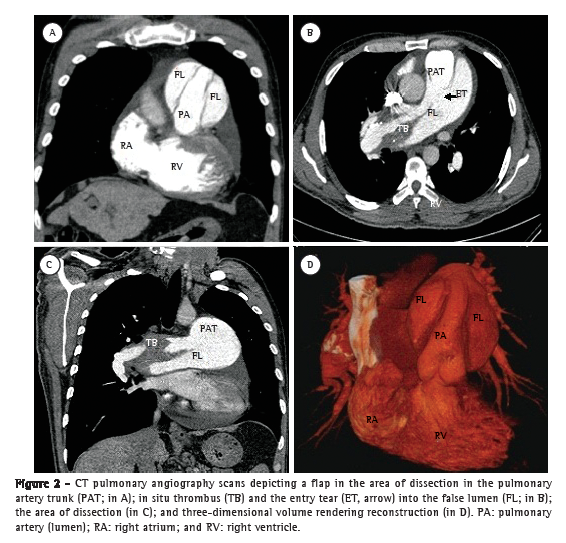

A 50-year-old male patient diagnosed four years prior with pulmonary hypertension related to schistosomiasis mansoni was admitted to the emergency room of the Federal University of Minas Gerais School of Medicine Hospital das Clínicas, located in the city of Belo Horizonte, Brazil. He presented with new onset, progressively worsening retrosternal chest pain and shortness of breath (functional class III pulmonary hypertension according to the World Health Organization). He had been diagnosed with chronic myeloid leukemia seven months prior and had since been on chemotherapy. At admission, transthoracic echocardiography revealed a large non-obstructive central thrombus in the right main pulmonary artery. The right atrium was dilated, and there was mild tricuspid regurgitation, with an estimated pulmonary artery systolic pressure of 63 mmHg. He was diagnosed as having in situ thrombosis as a complication of the long-standing pulmonary hypertension. After the possibility of acute coronary syndrome had been excluded, he was discharged on warfarin. He was re-admitted two months later due to progressively worsening, refractory chest pain. At that time, he had an SpO2 of 96%, and a third heart sound was audible at the lower left parasternal space, accompanied by a murmur of tricuspid regurgitation. The lungs were clear, and the peripheral arterial pulses were symmetric. Laboratory test results were unremarkable, including serum levels of creatine kinase, creatine kinase MB isoenzyme, and troponin. A resting electrocardiogram showed evidence of acute myocardial ischemia in the anterior leads. Transthoracic Doppler echocardiogram revealed a pulmonary artery systolic pressure of 62 mmHg, a thrombus in the right pulmonary artery, as in the previous examination, and the presence of a flap at that level that was compatible with pulmonary artery dissection (Figure 1). The diagnosis was confirmed by subsequent CT pulmonary angiography (CTPA; Figure 2). He was transferred to another cardiovascular treatment facility, where attempts were made to correct the defect with an endovascular procedure (via the femoral vein). During the perioperative period, the patient presented with refractory cardiogenic shock. Multiple efforts to resuscitate the patient were unsuccessful, and he died in the operating room.

To our knowledge, this is only the second report of a case of pulmonary artery dissection in a patient with schistosomiasis-related pulmonary hypertension, the first such case having been diagnosed at autopsy.(6) Clinically, these cases present with aggravation of previous symptoms of dyspnea and chest pain. The chest pain is typically sharp and can mimic acute coronary syndrome or acute aorta dissection. Cyanosis can be present.(7) The diagnosis is often obtained postmortem, because most patients die suddenly due to cardiac tamponade or severe pulmonary bleeding. If the diagnosis is made antemortem, the first finding is the emergence of a flap in the lumen of the dilated pulmonary artery or trunk formed from the intimal layer, denoting the entry tear into the false lumen but rarely an exit, which is the opposite of what is found in cases of aortic dissection.(8) Magnetic resonance imaging or CTPA of the chest can confirm the diagnosis and the associated complications, such as an increase in pulmonary artery dilatation, bloody pleural fluid, and pulmonary opacities.(1) The evolution is usually rupture of the vessel with blood flowing into the mediastinum, pericardium, or lung, because there is no exit from the false lumen. The intimal tear that leads to the dissection occurs at the point of greatest dilatation as a consequence of an increased parietal tension. It has been reported that inflammation due to in situ thrombosis can play a synergistic role in the development of the intimal disruption.(4,9,10)